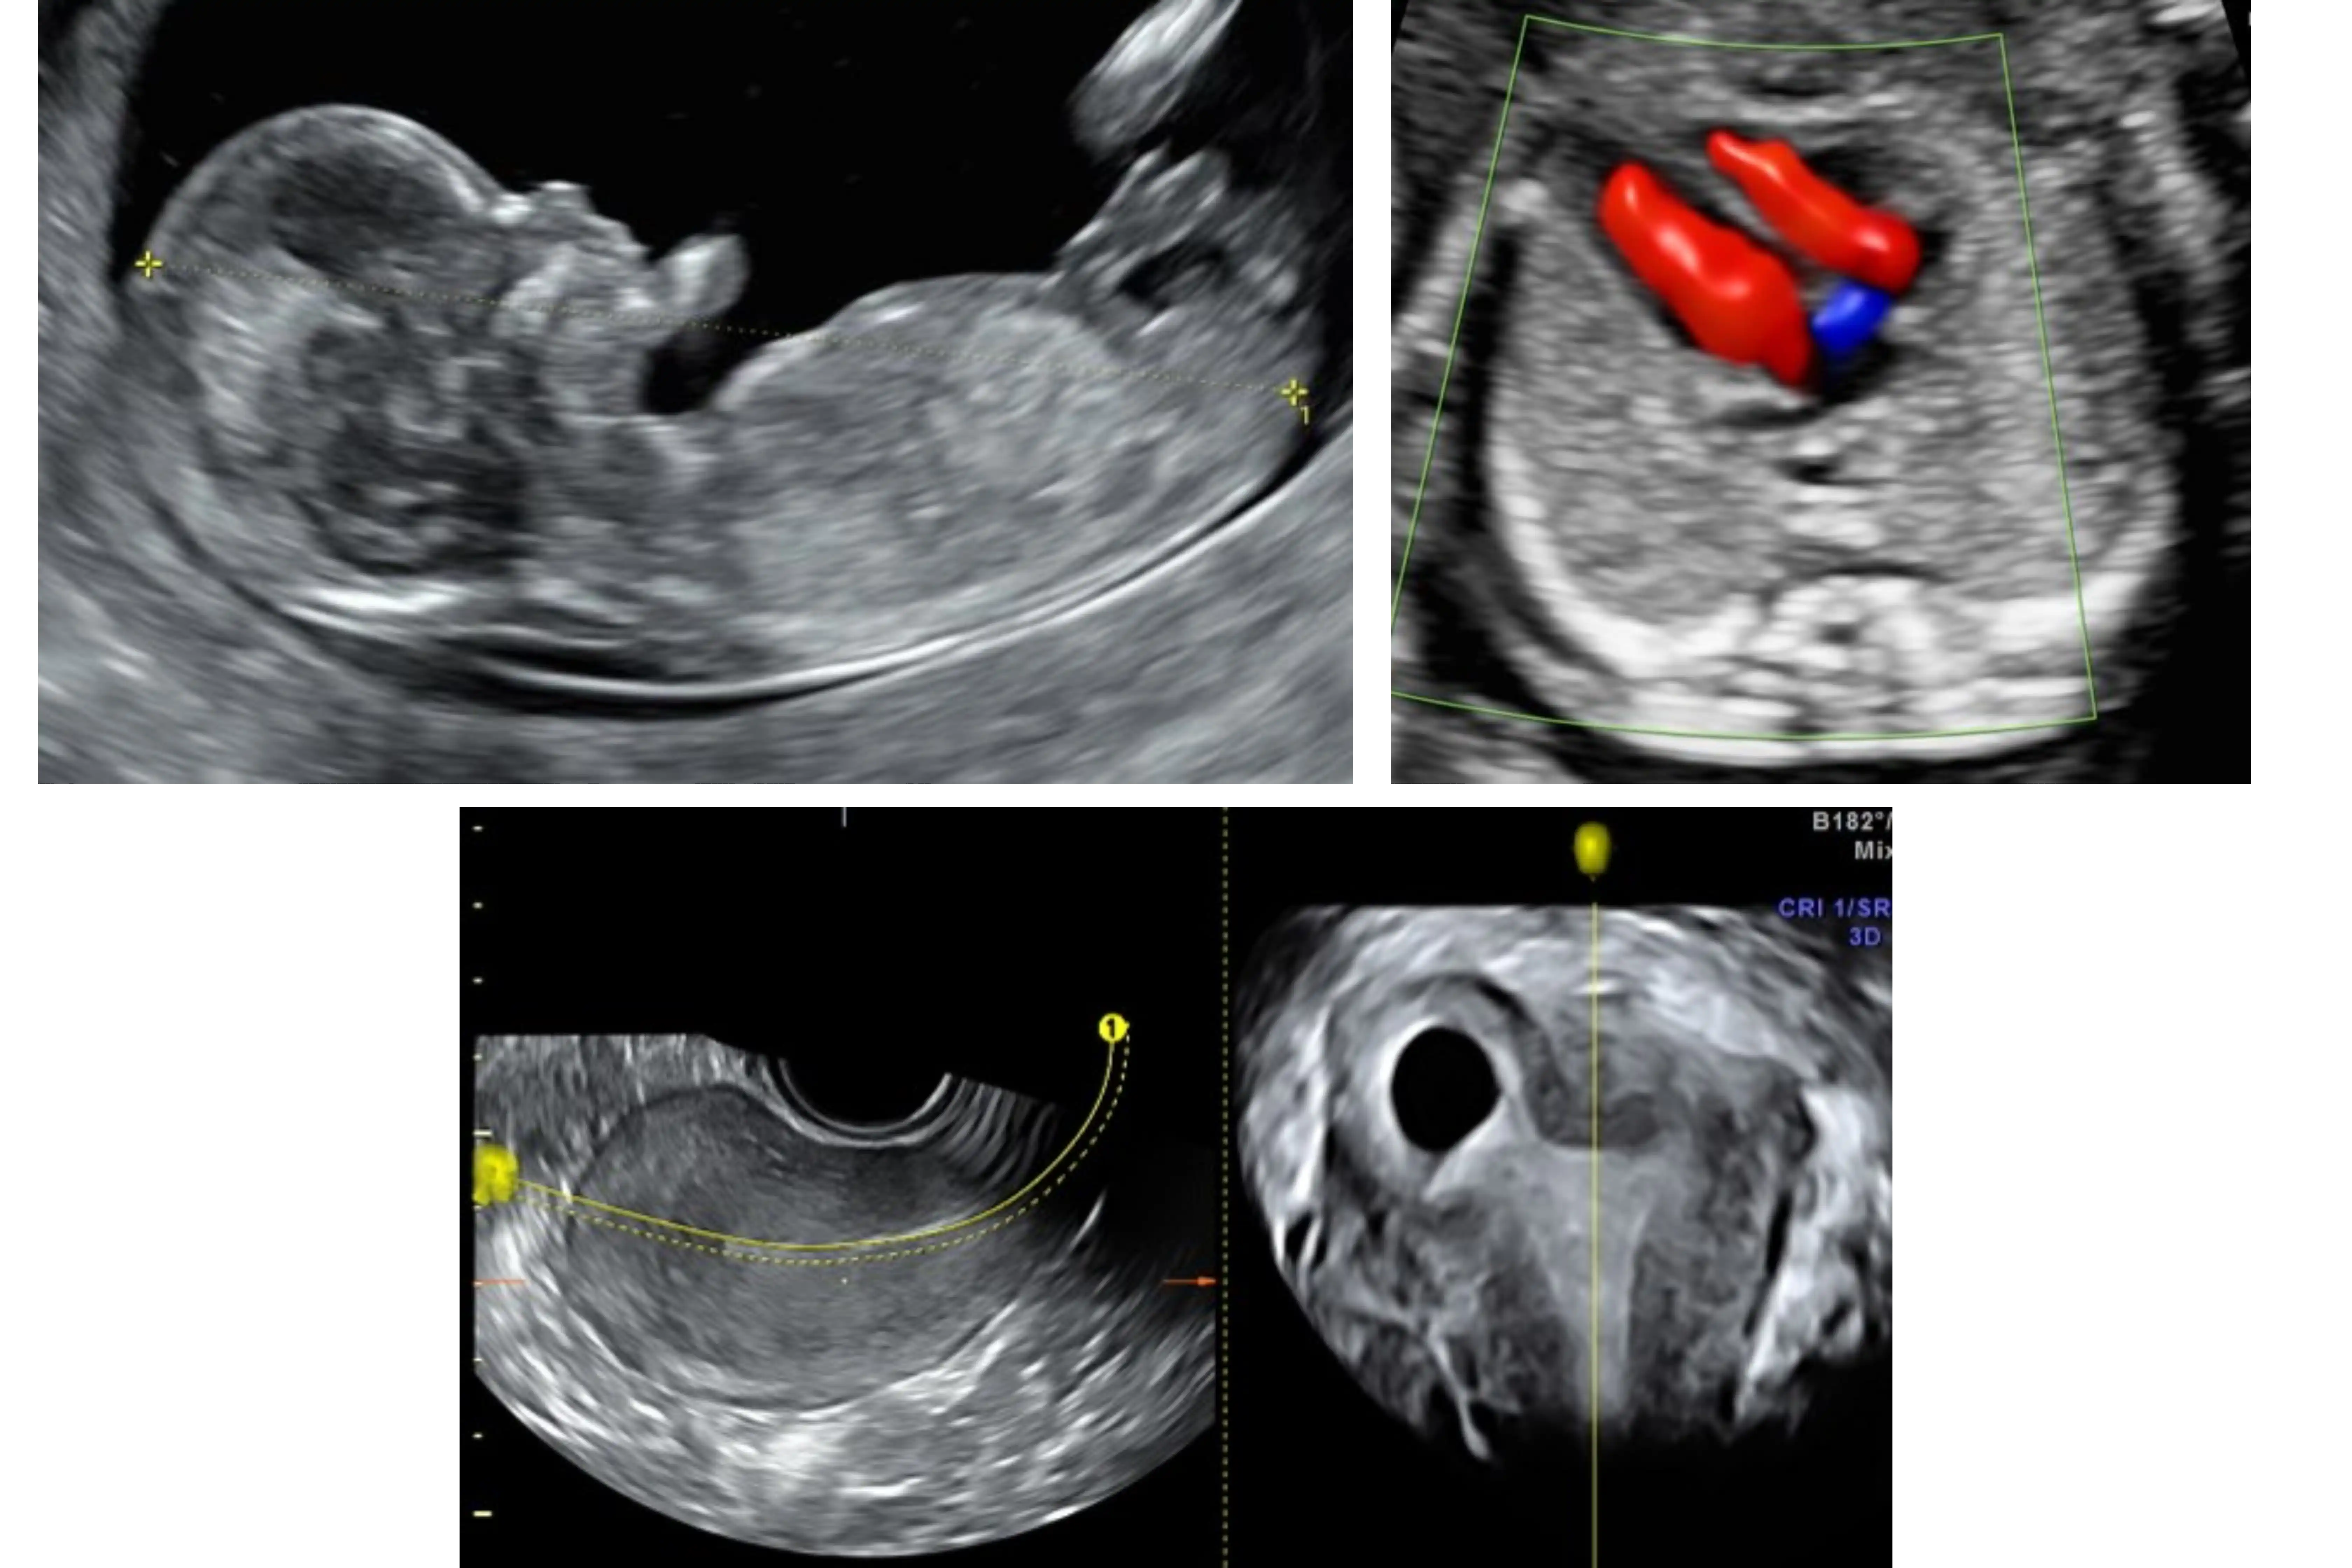

1c. Advanced 3D/4D workshop

Understanding Acquisition, Manipulation of 3D volumes in First Trimester

Skeletal System

Fetal Vascular System

Fetal Brain

Use of STIC - Cardiac 4D